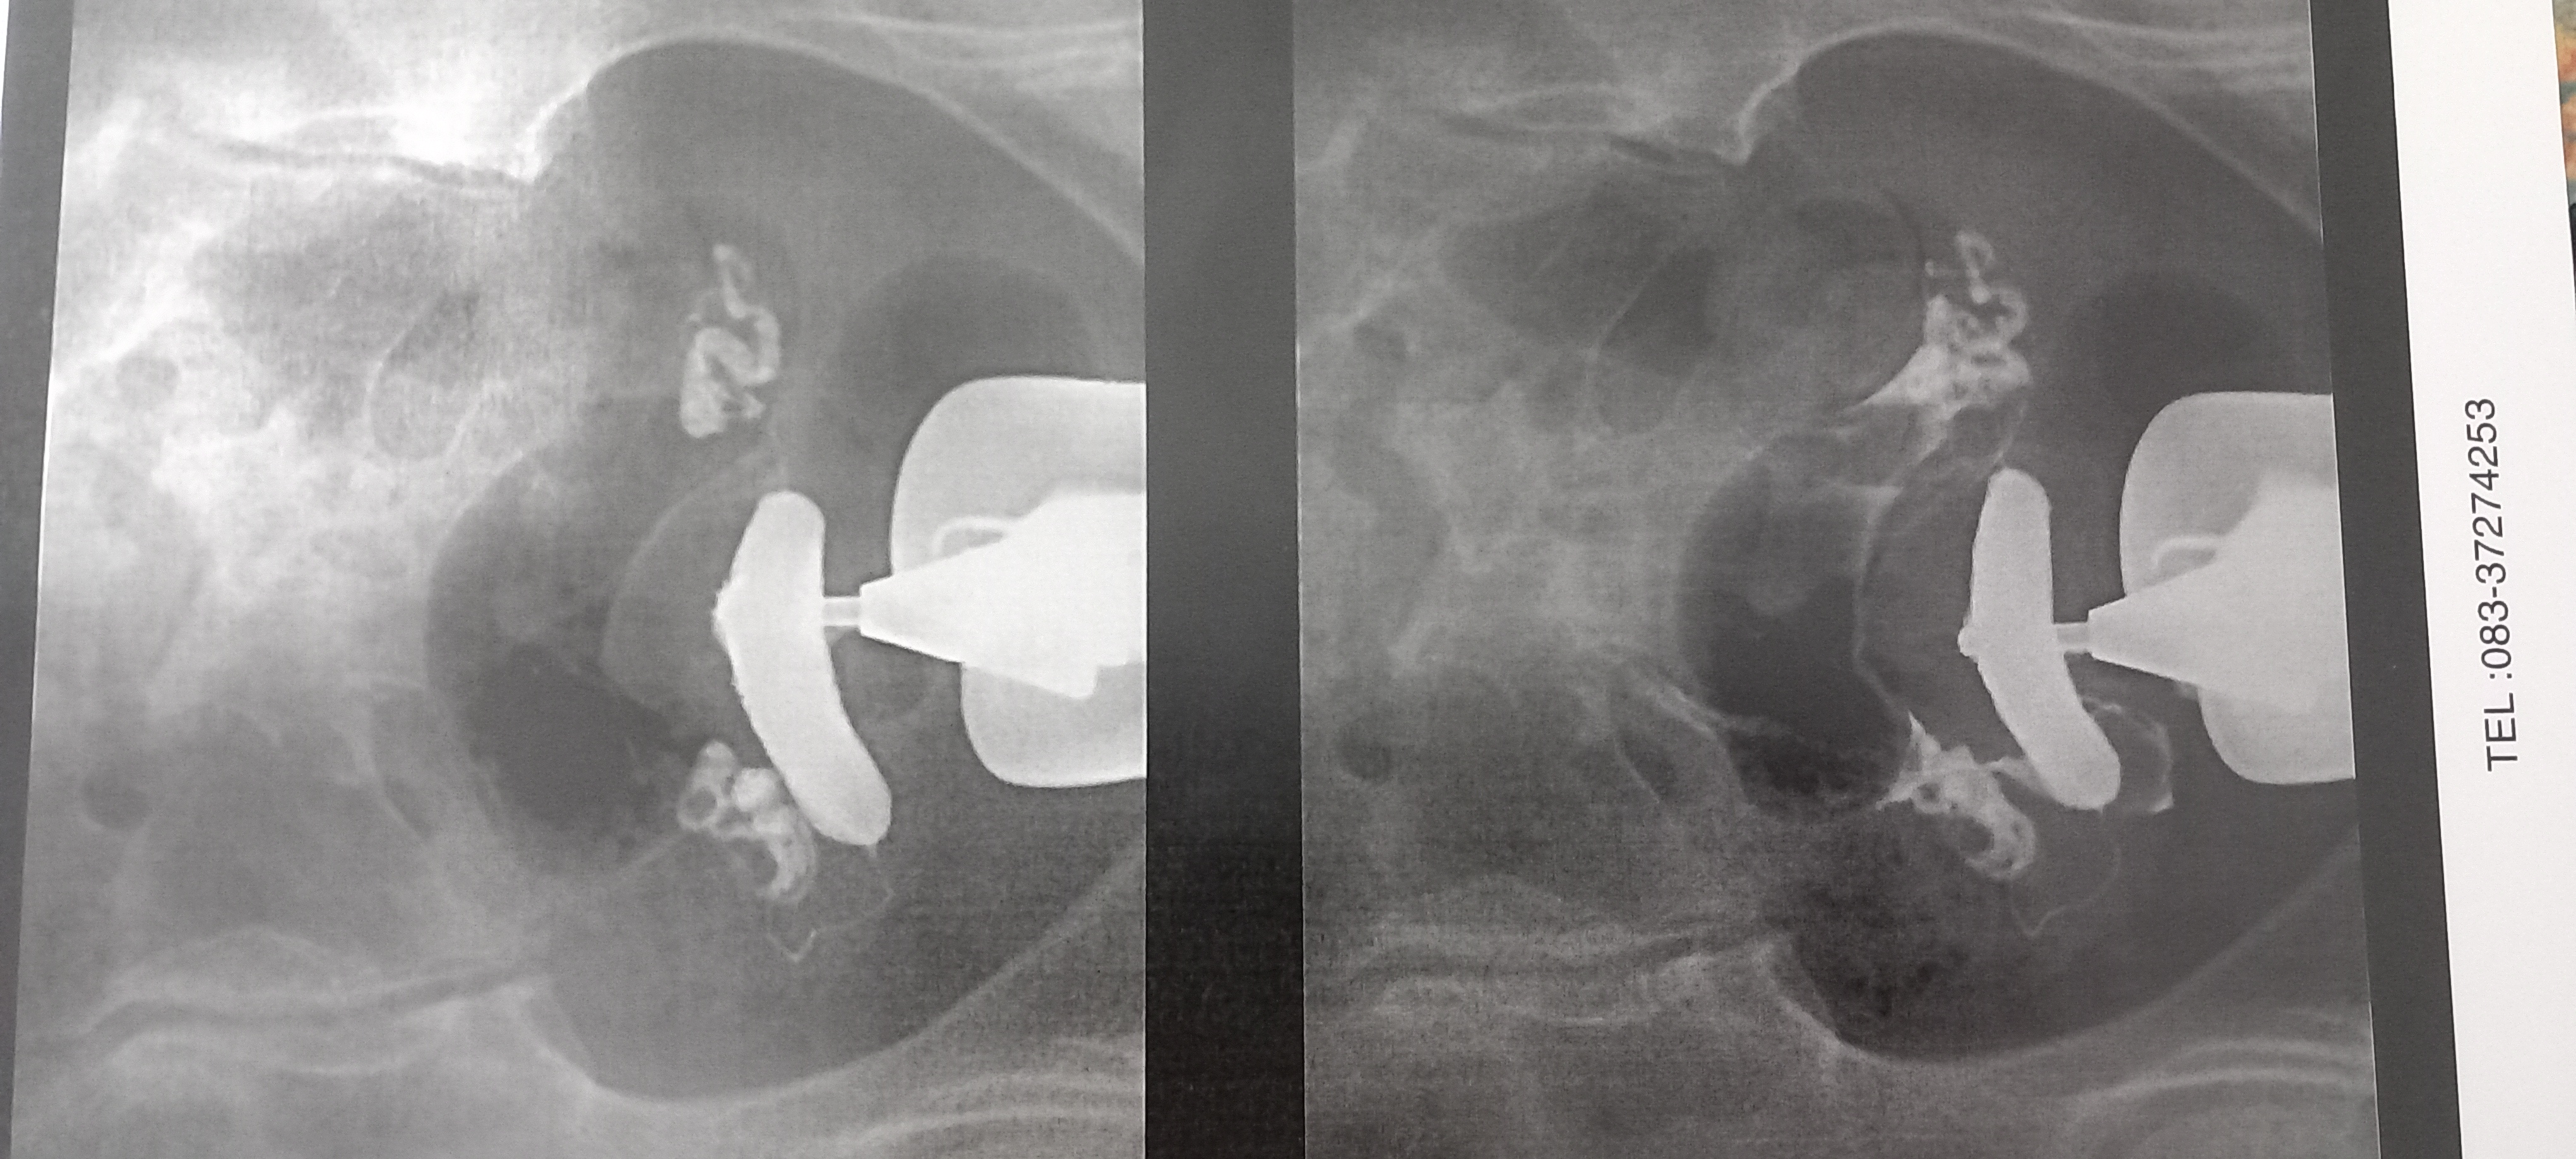

پاتریک75 مدیر استارتر عضویت: 1403/05/15 تعداد پست: 266 عنوان تفسیرعکسرنگیرحم بیاید خواهش میکنم 17 بازدید | 1 پست چرا اینطوریه شبیه عکسایی ک از نت دیدم نیستمشکلی هست اگ میدونید بگید توروخدا 1403/08/02 | 20:33 0 نفر لایک کرده اند ... گزارش تاپیک نامناسب